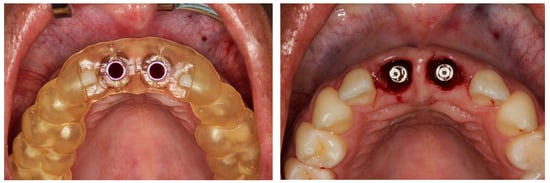

2.4. Virtual Planning

2.5. Surgical Procedures